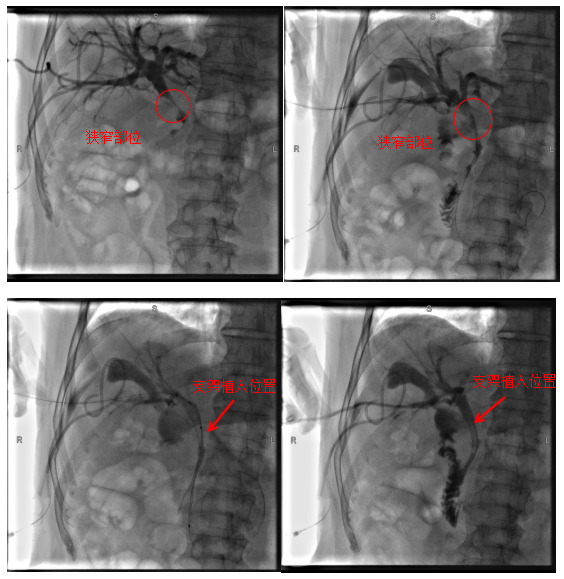

术中影像